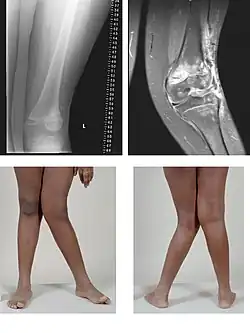

Am Kniegelenk ist dies eine Abweichung des Unterschenkels nach außen, was einem X-Bein entspricht, wenn die normale X-Stellung (physiologische Valgusstellung) von 7 Grad überschritten ist; dadurch sind die inneren Gelenkanteile oft hervorstehend. Der Fachterminus ist das Genu valgum.

Bei einem X-Bein (Genu valgum) kann dies durch eine vermehrte Belastung des äußeren Gelenkspaltes zu einer außenseitig betonten Valgus-Gonarthrose führen.